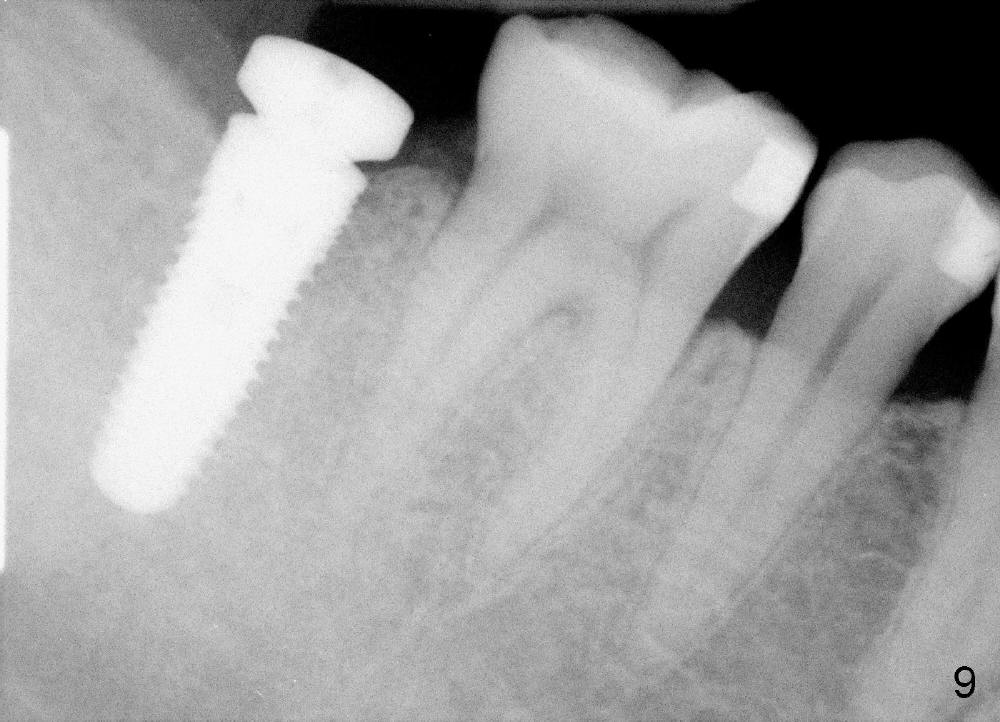

A 53-year-old man requests implant restoration for the lower right 2nd molar (Fig.1: LR2). A 5.3x14 mm submerged tapered implant is planned (Fig.2). PA is taken with a parallel pin after use of a 2 mm drill at the depth of 12 mm (Fig.3). It appears that the length of 14 mm has a safe margin (2-3 mm from the inferior alveolar nerve, yellow dashed line). In addition, the distance from the distal surface of the 1st molar is within normal limit (~5 mm).

With these two parameters under control, it is quick and safe to finish osteotomy with tapered drills with stoppers (Fig.4 <). Stoppers are particularly useful in the posterior region where visibility is limited. The implant is placed as planned (Fig.5, as compared to Fig.2).